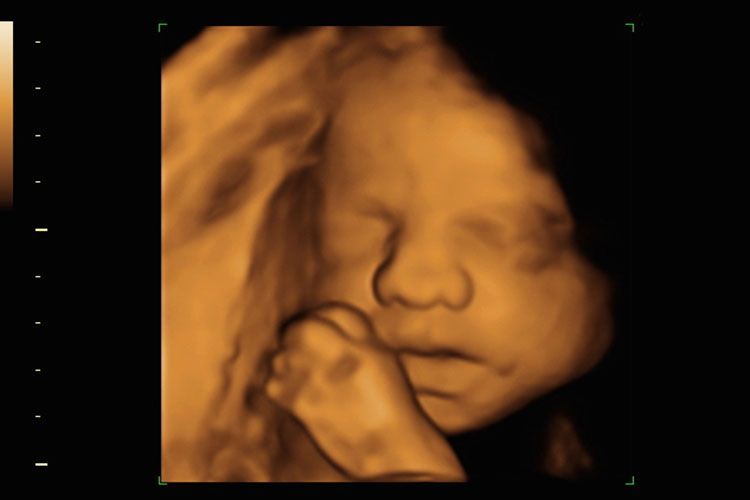

Of je nu voor een medische echo komt of een pretecho om alvast een glimp van je kindje op te vangen, wij zorgen ervoor dat je je welkom en op je gemak voelt. Onze deskundige en vriendelijke medewerkers staan klaar om je te begeleiden en te voorzien van de informatie die je nodig hebt.